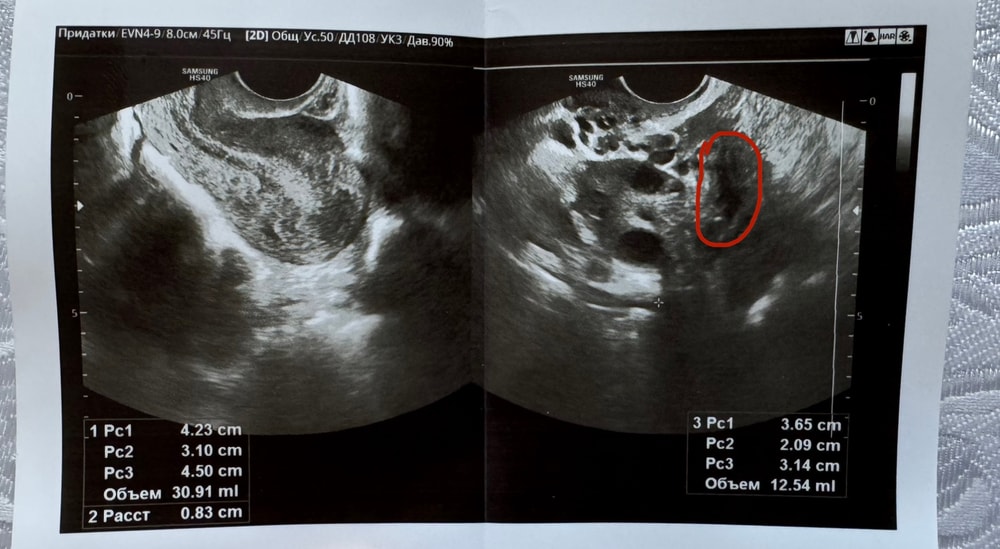

Врач мне про желтого тело нечего не сказала

Я и сама не спросила

Сказала что Овуляция была

И написано что есть умеренное жидкость позади маточного пространства

Мне кажется на фоте это Жт?